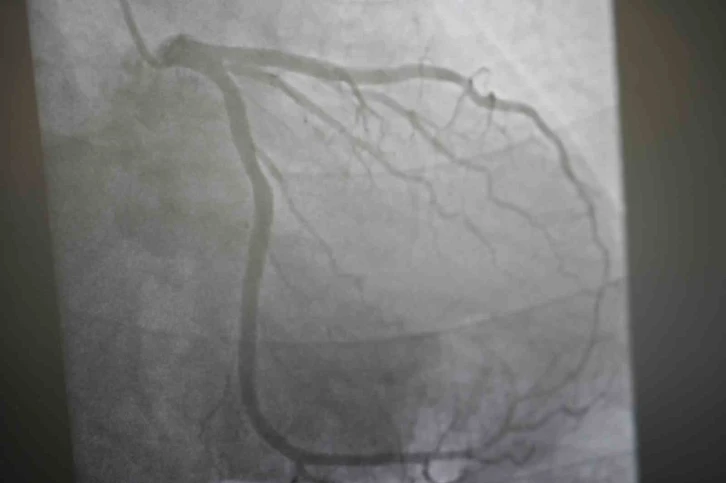

Aşıların kalp krizi riskine etkileri üzerinde açıklamalarda bulunan Medicana International Samsun Hastanesi Kardiyoloji Kliniğinden Prof. Dr. Uğur Arslan, “Covid-19 salgını sonrası kalp krizi olaylarında bir nebze artış hissettik. Ancak bu aslında beklenen bir şey. Direkt aşıları da suçlamamak gerekiyor. Çünkü aşılar hastalığı bir şekilde taklit ettikleri için insana daha hafif dokunsun diye bir miktarda olsa bu riski arttırabilirler. Covid’i bir grip gibi de düşünebilirsiniz. Artık yeni nesil grip biraz daha ağır geçiyor. Bu viral hastalıklar zaten genel olaraktan inflamatuar süreci başlattığı için kalp krizi gibi, koroner arter hastalığı inme gibi riskleri de arttırabilmektedir. Aşılar da bunlara dahildir. Az da olsa arttırmaktadır ama genel olarak bakıldığında kalp krizi için kişi Covid geçirseydi daha yüksek riske sahip olurdu diyebiliriz” diye konuştu. Sıcak havaların kalp hastaları üzerindeki etkileri